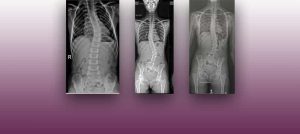

Institut Chiari & Siringomielia & Escoliosis de Barcelona is highly specialized neurosurgical center dedicated to the diagnosis and treatment of spinal and brain disorders, with a focus on the clinical concept of Filum Terminale Disease. Conditions treated include: